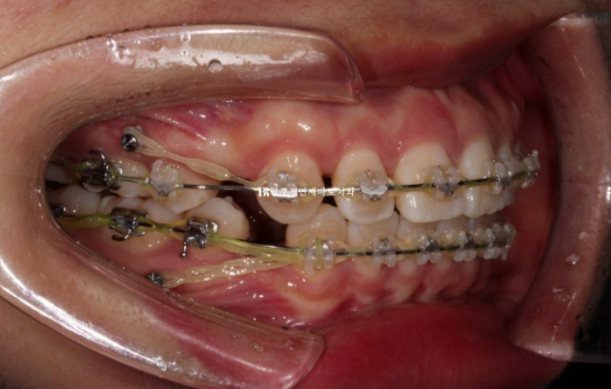

23.09

치료시작 7개월째 모습입니다.

이제 막 발치공간이 없어지면서 앞니가 뒤로 들어가기 시작하는 단계입니다.

24.03

치료시작 1년 1개월째 사진입니다.

발치공간은 모두 없어졌고 미니스크류를 이용하여 중심선을 맞추고 있습니다.

마무리 과정이라고 부르는 단계입니다.